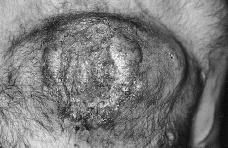

En la exploración física el enfermo presentaba un buen estado general, observándose en pared anterior del tórax una tumoración de aproximadamente 15 cm de diámetro mayor que se elevaba unos 3-4 cm sobre la superficie cutánea, de coloración violácea, superficie irregular erosionada, consistencia dura con áreas de necrosis en su interior y gran infiltración de la base (Fig. 1). El resto de la exploración física estuvo dentro de la normalidad.

FIG.1.--Lesión tumoral en tórax correspondiente a un plasmocitoma cutáneo secundario a mieloma múltiple.